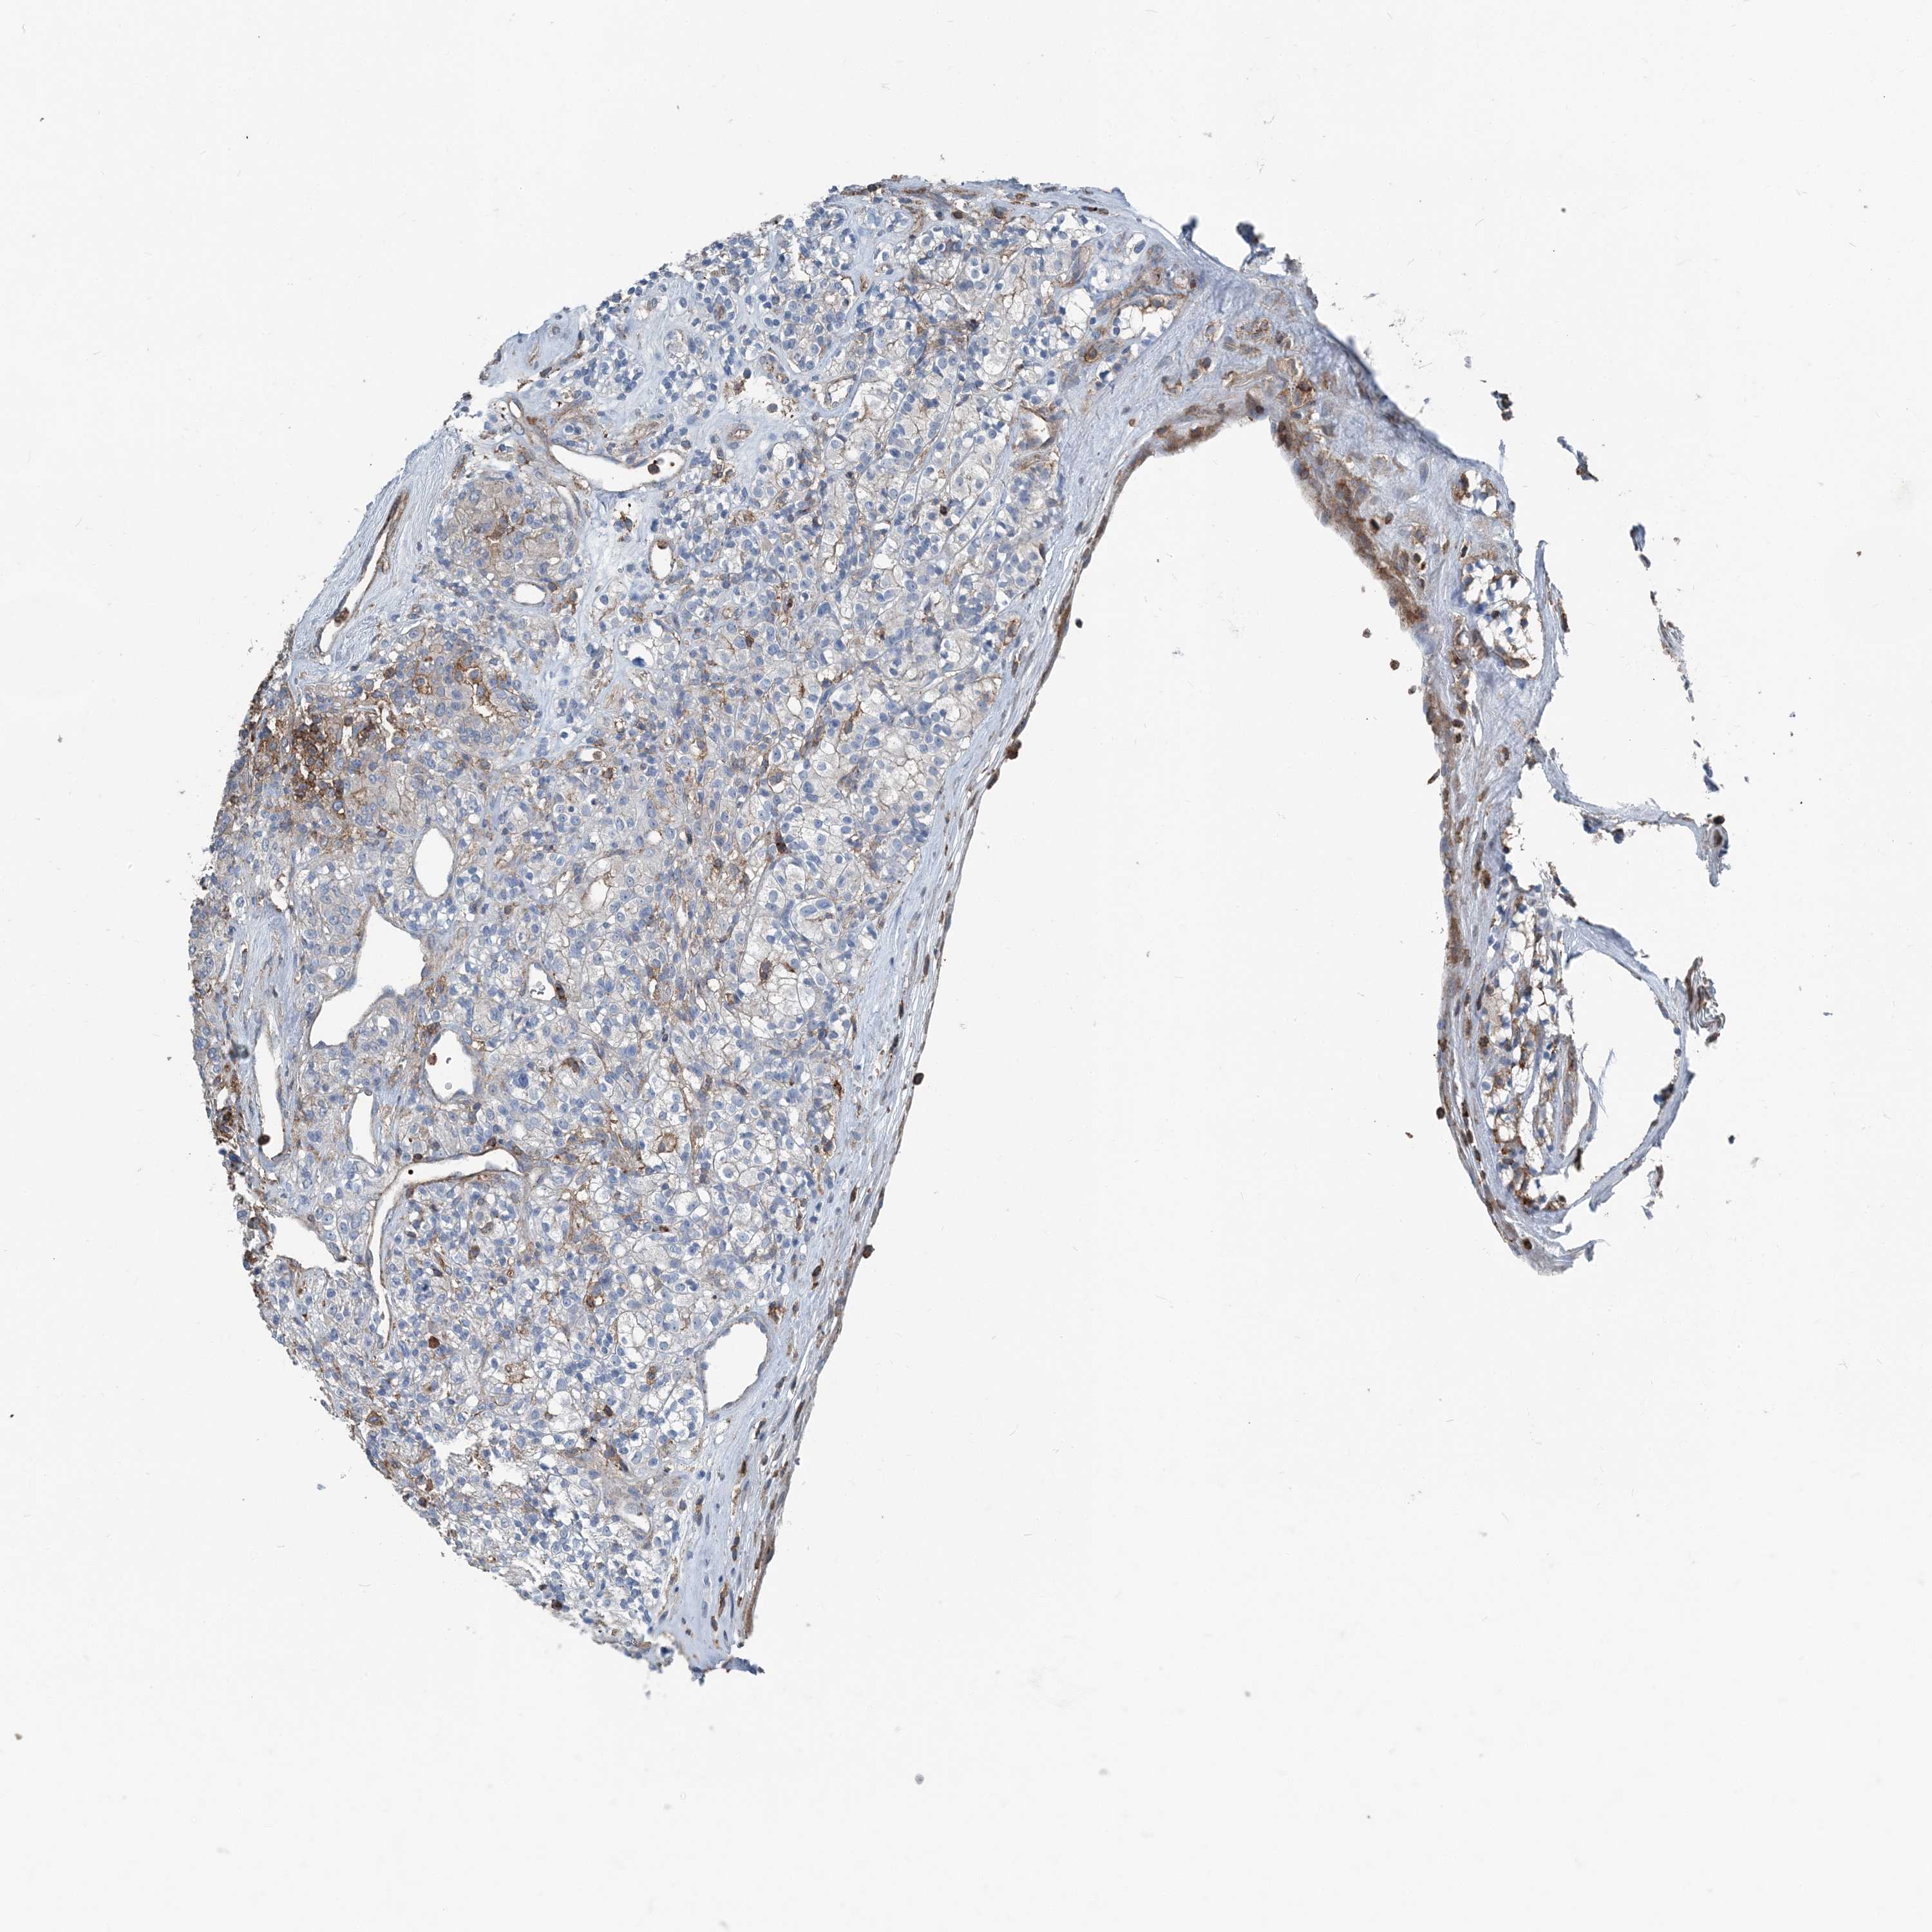

KIDNEY RENAL CLEAR CELL CARCINOMA (VALIDATION) - Interactive survival scatter ploti

The Survival Scatter plot shows the clinical status (i.e. dead or alive) for all individuals in the patient cohort, based on the same data that underlies the corresponding Kaplan-Meier plots. Patients that are alive at last time for follow-up are shown in blue and patients who have died during the study are shown in red.

The x-axis shows the expression levels (FPKM) of the investigated gene in the tumor tissue at the time of diagnosis. The y-axis shows the follow-up time after diagnosis (years). Both axes are complimented with kernel density curves demonstrating the data density over the axes. The top density plot shows the expression levels (FPKM) distribution among dead (red) and alive patients (blue). The right density plot shows the data density of the survived years of dead patients with high and low expression levels respectively, stratified using the cutoff indicated by the vertical dashed line through the Survival Scatter plot. This cutoff is automatically defined based on the FPKM cutoff that minimizes the p-score. The cutoff can be changed by dragging the vertical line or by entering a cutoff value in the square labeled "Current cut-off".

Under the Survival Scatter plot the p-score landscape (black curve; left axis) is shown together with dead median separation (red curve; right axis). Dead median separation is the difference in median mRNA expression between patients who have died with high and low expression, respectively. It is calculated as follows: median FPKM expression of dead patients with high expression - median FPKM expression of dead patients with low expression. This is intended to aid the user in visually exploring custom cutoffs and the associated p-scores and dead median separation.

Individual patient data is displayed and can be filtered by clicking on one or more of the category buttons on the top of the page. Categories describing expression level and patient information include: high, low, alive, dead, female, male and tumor stages. The scale of the x-axis can be toggled between linear and log-scale by clicking on the "x log" button. Mouse-over function shows TCGA ID, patient information and mRNA expression (FPKM) for each patient.

& Survival analysisi

Kaplan-Meier plots summarize results from analysis of correlation between mRNA expression level and patient survival. Patients were divided based on level of expression into one of the two groups "low" (under cut off) or "high" (over cut off). X-axis shows time for survival (years) and y-axis shows the probability of survival, where 1.0 corresponds to 100 percent.

CFL1 is not prognostic in Kidney Renal Clear Cell Carcinoma (validation)

Best expression cut offi

Based on the FPKM value of each gene, patients were classified into two groups and association between prognosis (survival) and gene expression (FPKM) was examined. The best expression cut-off refers the FPKM value that yields maximal difference with regard to survival between the two groups at the lowest log-rank P-value. Best expression cut-off was selected based on survival analysis .

When clicking on this number, the vertical dashed line indicating cut-off, the interactive survival plot, and the Kaplan-Meier curve will be adjusted to show results based on the best expression cut-off.

: 750.87

TCGA RNA samplesi

RNA-seq data is reported as average FPKM (number Fragments Per Kilobase of exon per Million reads), generated by the The Cancer Genome Atlas (TCGA) .

Normal distribution across the dataset is visualized with box plots, shown as median and 25th and 75th percentiles. Points are displayed as outliers if they are above or below 1.5 times the interquartile range. FPKM values of the individual samples are presented next to the box plot.

Average pTPM 641.0

Number of samples 100